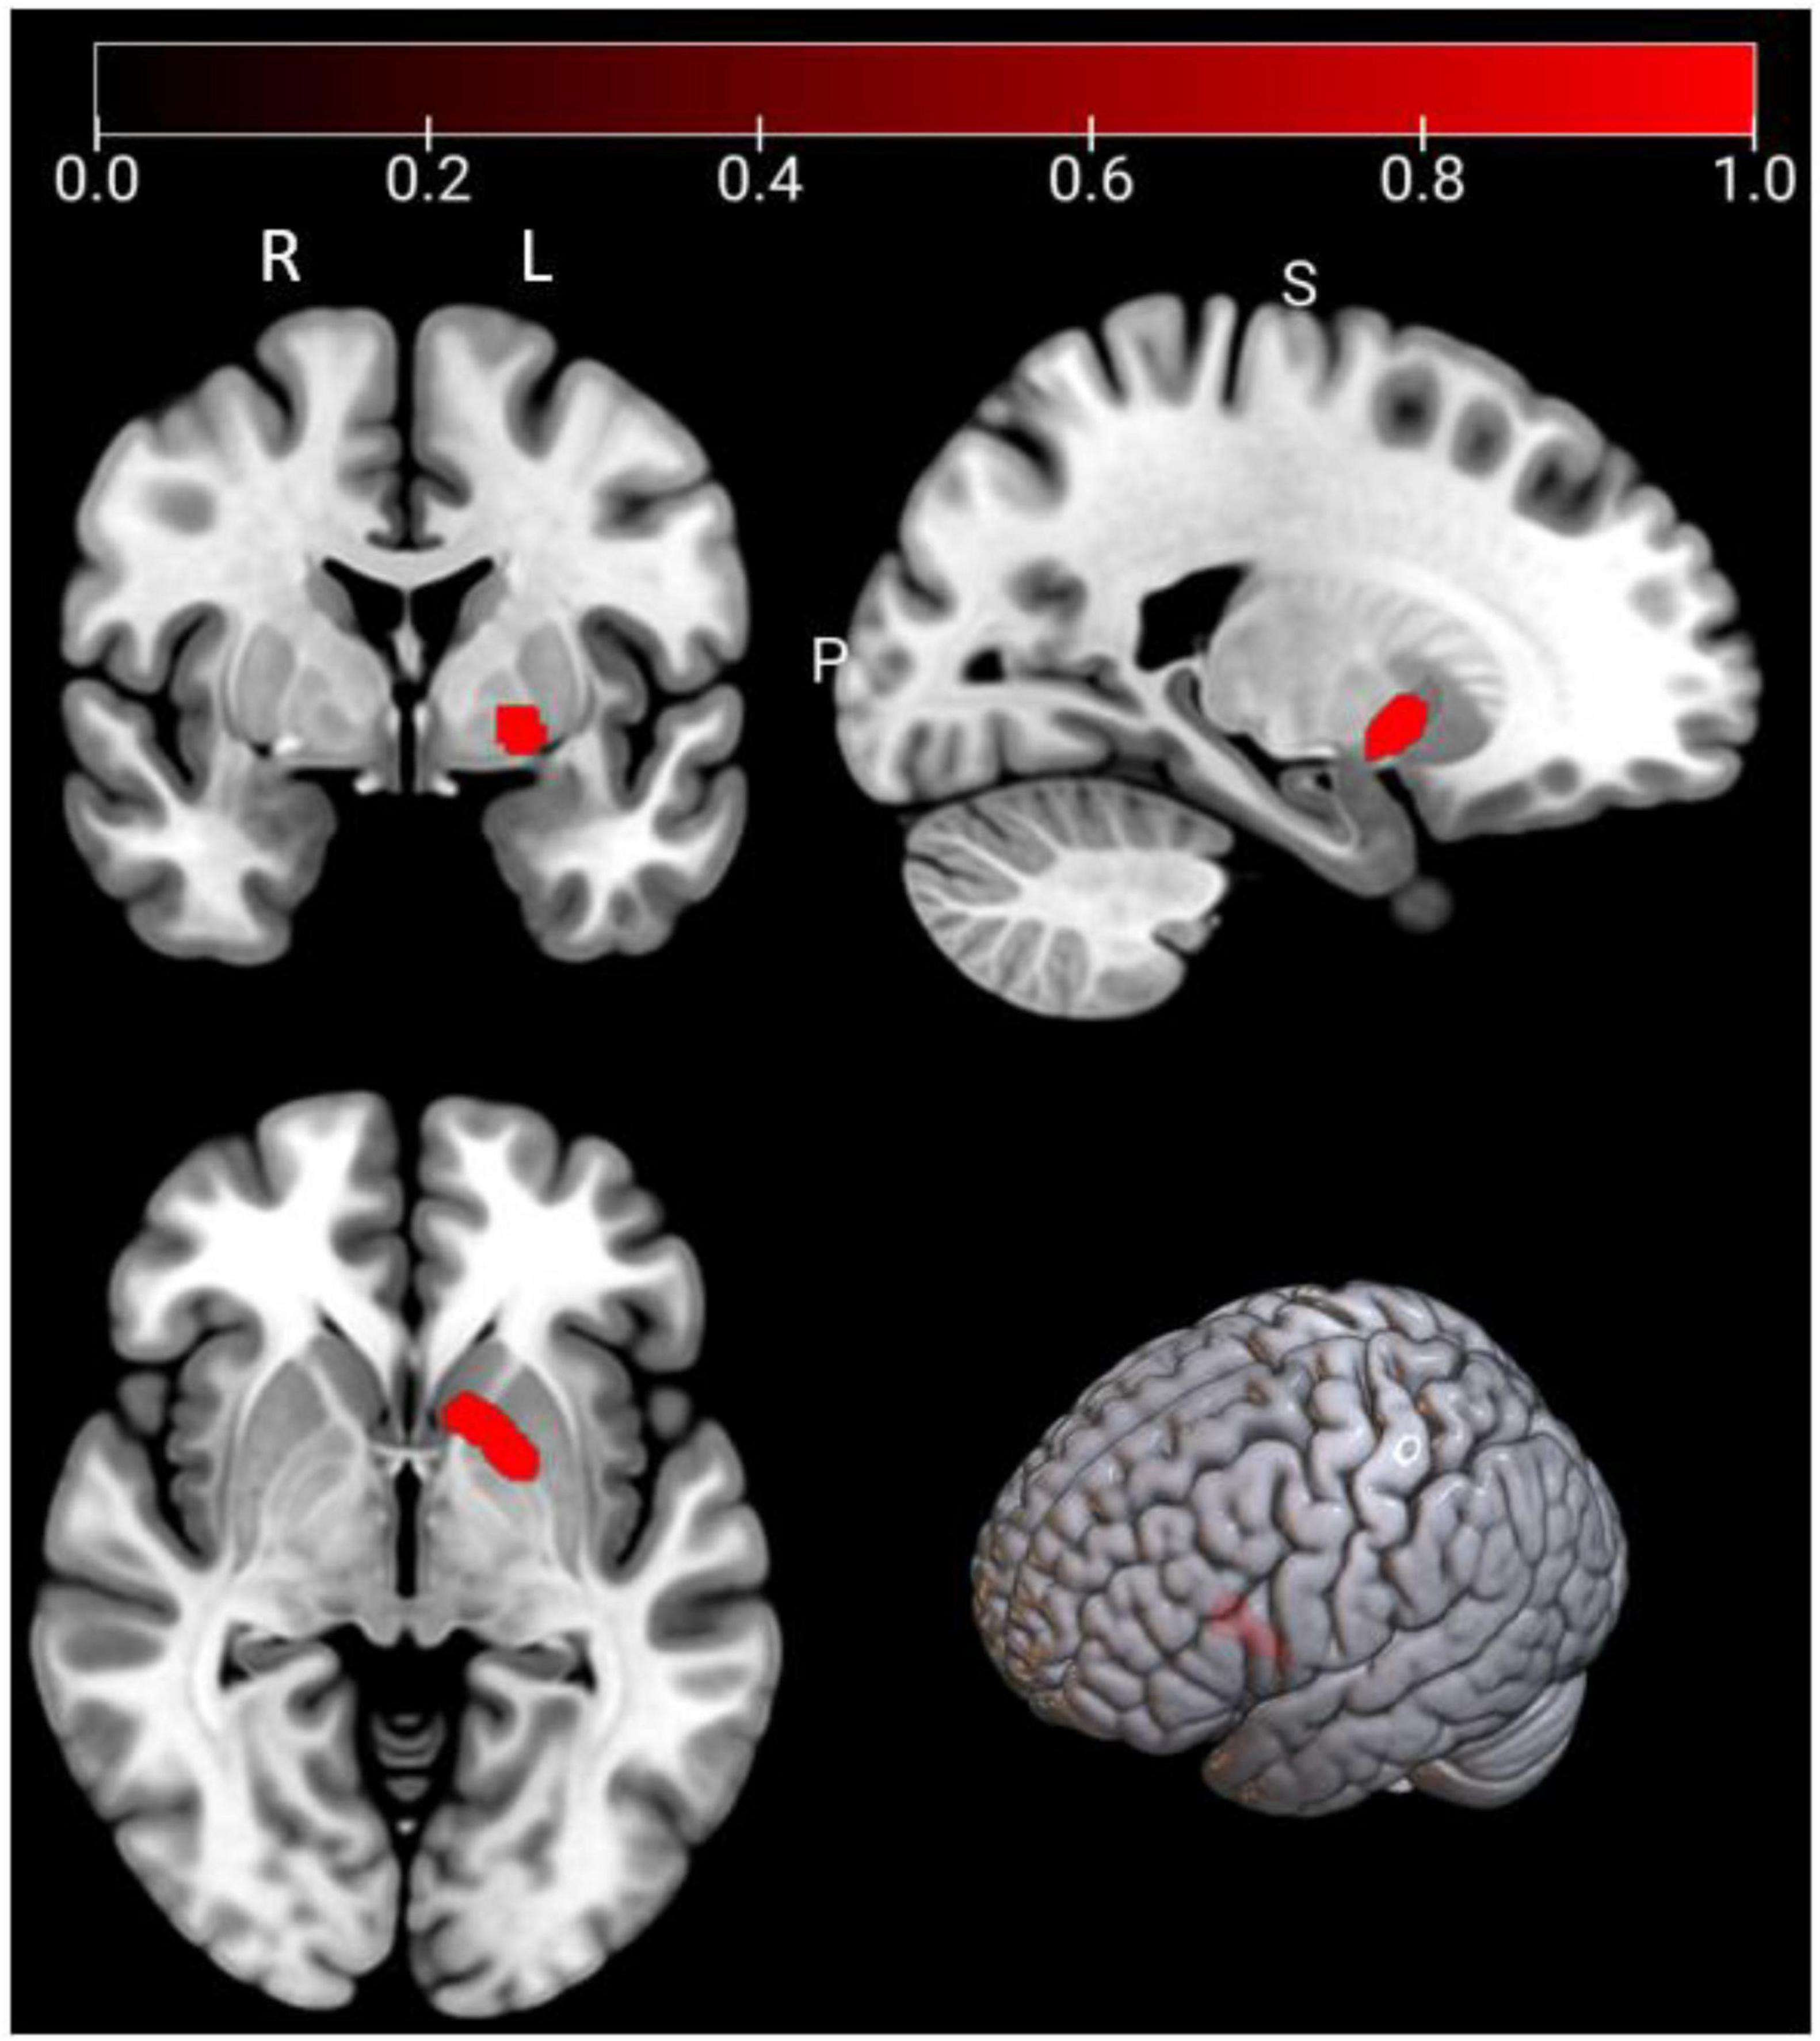

As Figure 5 and Table 5, a significant cluster was observed in the ALE meta-analysis results of resting-state fMRI studies in the right STG. This finding was also further validated by jackknife analyses, indicating robustness and high replicability in both observed clusters of right STG (6 out of 7 replicabilities); see Supplementary Table 4 for more details.

FIGURE 5

MRI brain scans showing different views: coronal, sagittal, and axial, alongside a 3D brain model. A red dot highlights a specific area, with a color scale from zero to one indicating intensity.

Figure 5. Emotional well-being (EWB) meta-maps (marked with red) of resting-state functional magnetic resonance imaging (fMRI) studies (the task-independent modality). “L” refers to the left hemisphere, and “R” refers to the right hemisphere.